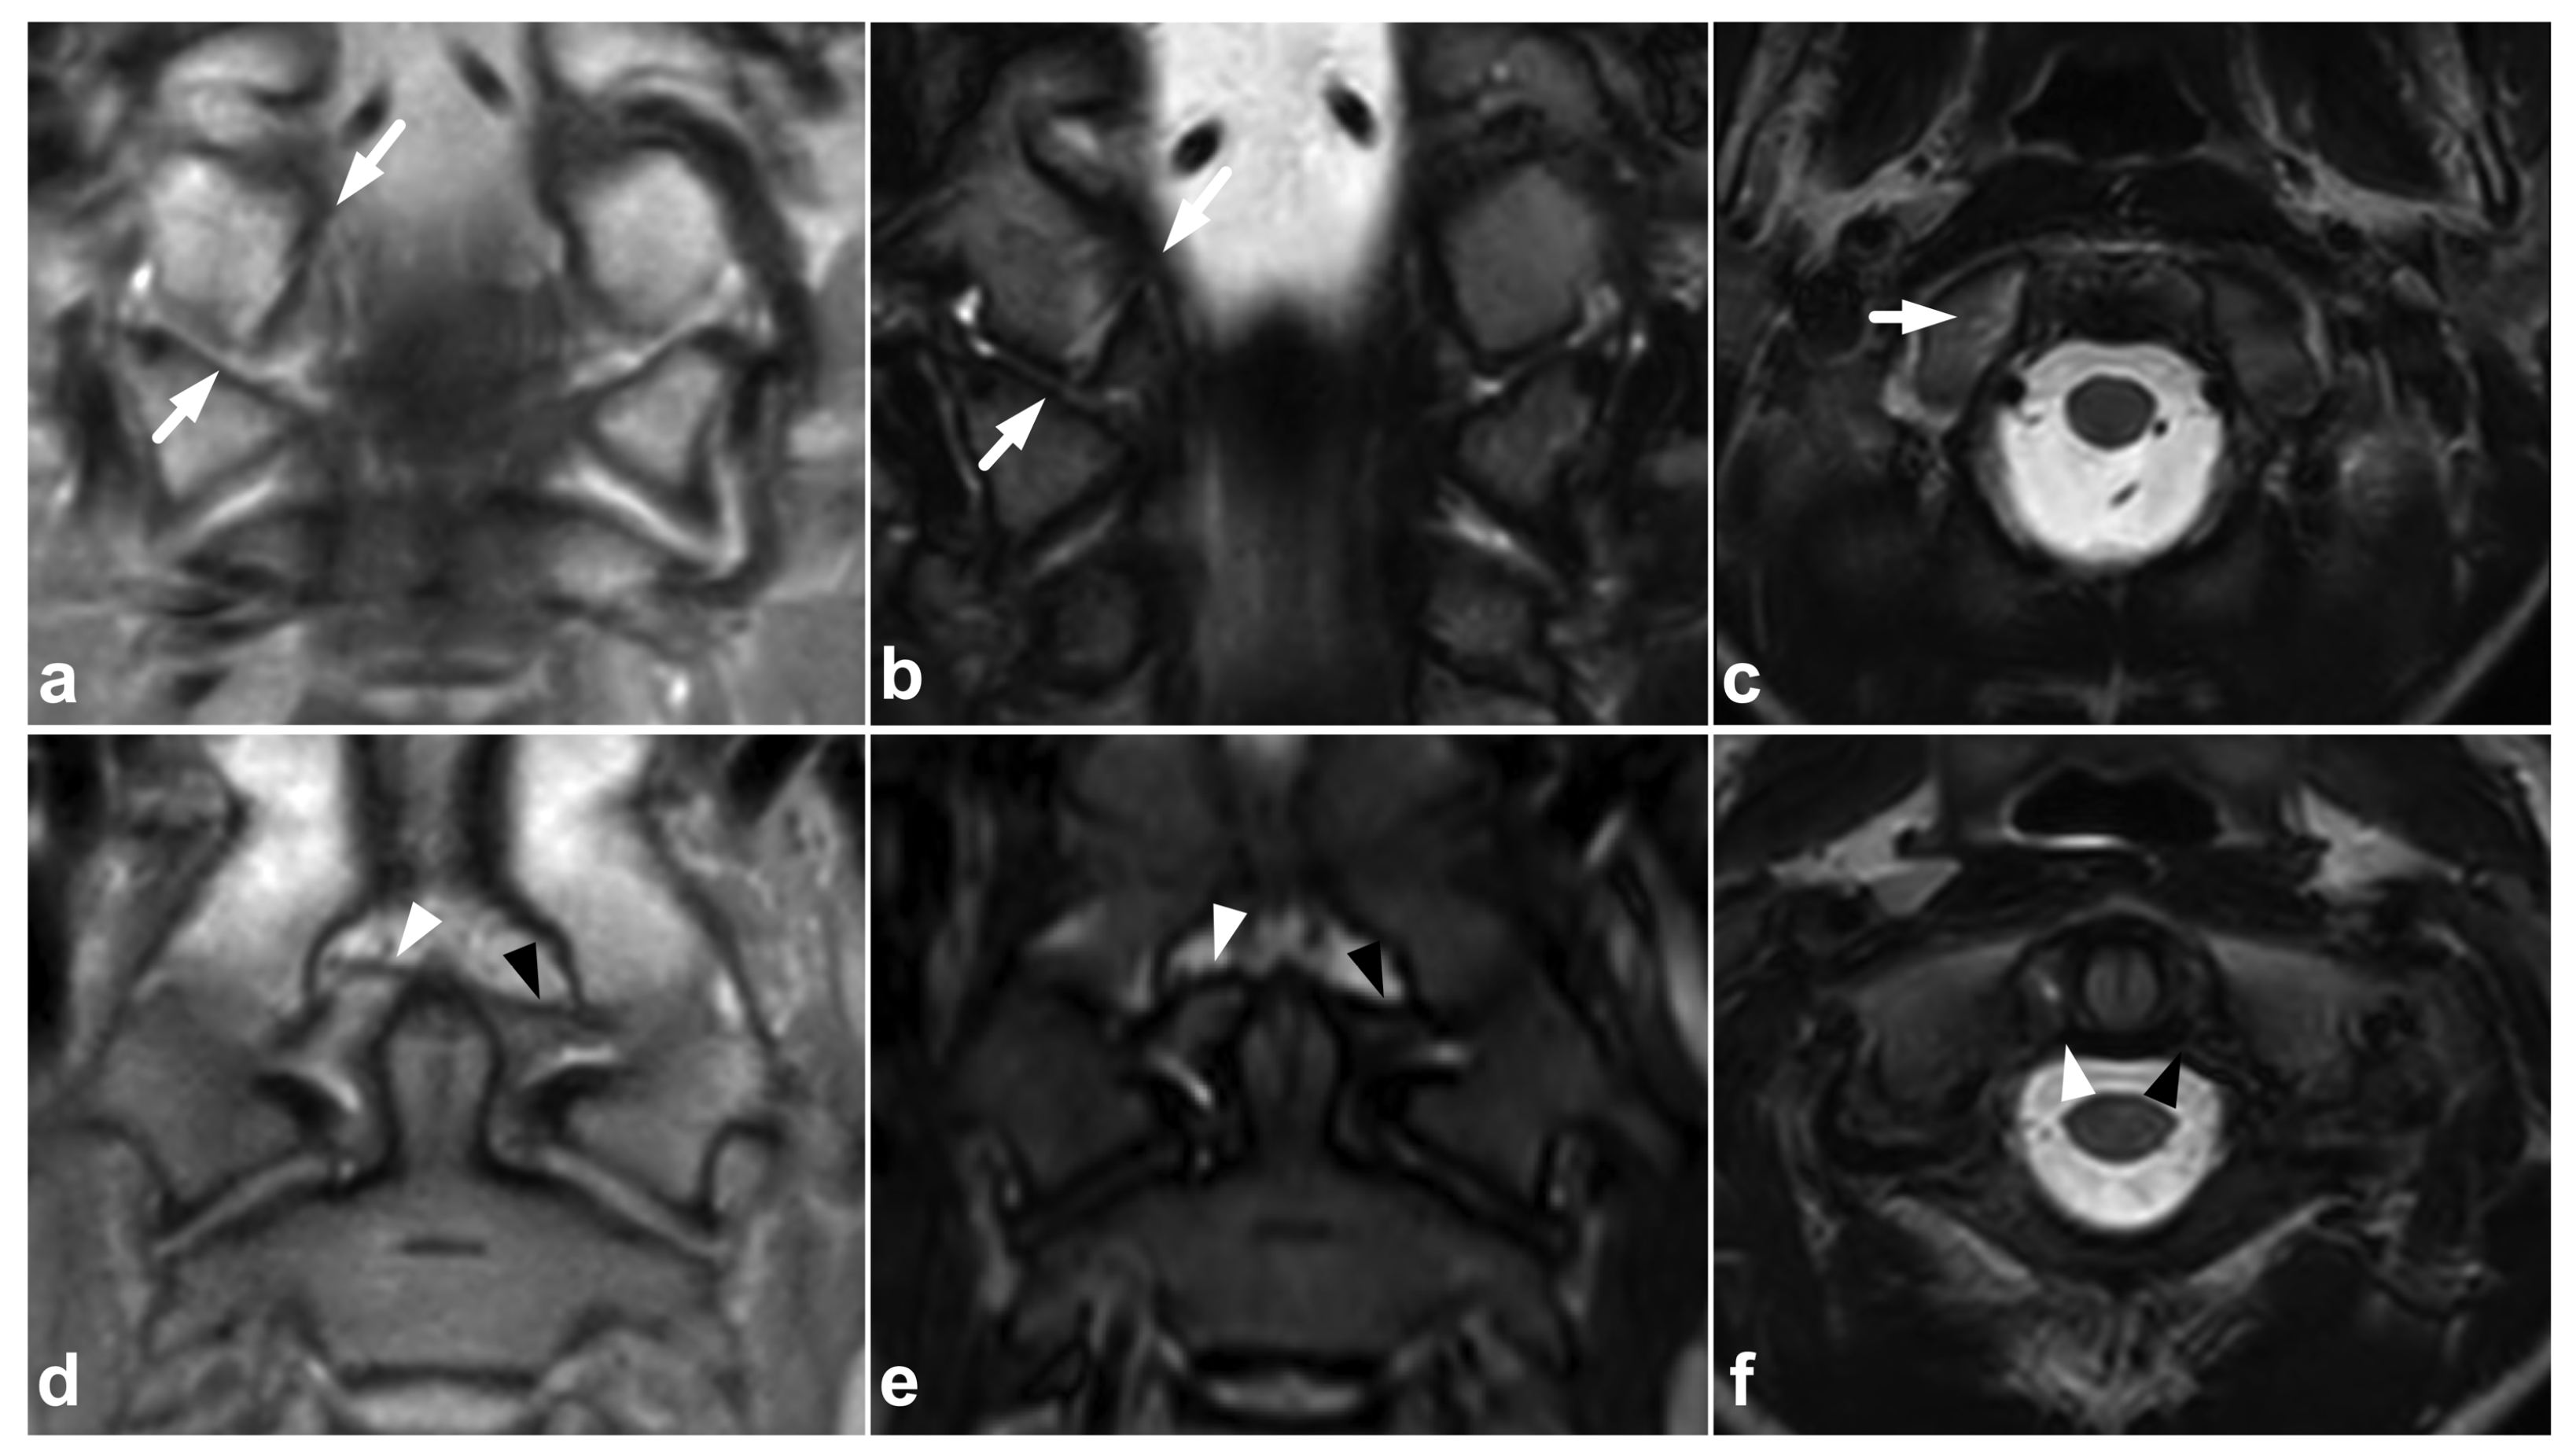

4.1. Occipitocervical and Atlantoaxial Ligaments